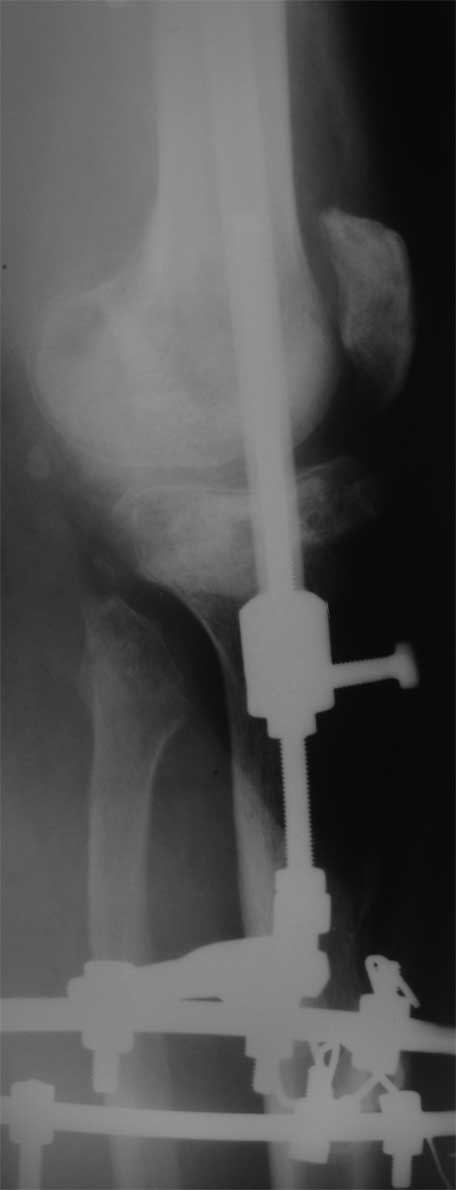

Поступил пациент 40 лет

Производственная травма. Лечился в гнойной хирургии - обширные раны голени.7 мес

пребывания в аппарате (на фото), по УЗИ - тромбоз глубоких вен с признаками реканализации.

Какую тактику лечения предпочесть? Планирую замещение костного дефекта цементом с а/б,

укрыть латеральной головкой икроножной мышцы, на нее кожную пластику. Опыта подобных

операций нет, переправить пациентка в другое более сведущее ЛПУ не получается (ко всему

прочему пациент абсолютно без денег, производство исчезло) Предпочесть другие варианты,

какие? Помогите с материалами по теме, книги, презентации, видео) Master technic b color

atlas у меня есть) Заранее благодарен.